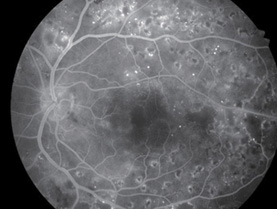

In addition to non-mydriatic color, mydriatic color, fluorescein angiography (FA), Red-free (RF), fundus autofluorescence (FAF*) is added to allow 5 photography modes.

Fundus Autofluorescence (FAF*)

Photo : Showa University